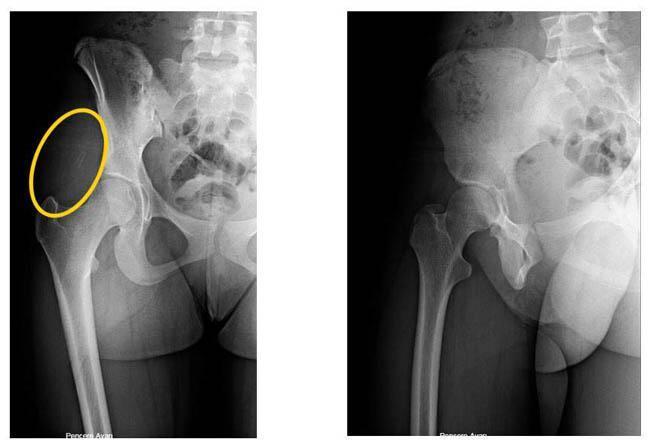

İstanbul'da şoke eden olay! Genç kızın kalçasından çıktı, doktorlar inanamadı

14 yaşındaki ortaokul öğrencisi H.A. 2017 yılının Şubat ayında karda kayıp düştü. Sert bir şekilde kalçasının üstüne düşen genç kız kalçasında bir ağrı hissetmeye başladı. Eve gittiğinde bir kalem ucu gören genç kız ağrısının nedenini buna bağladı ancak geçmeyince doktora gitti.